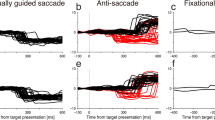

When tDCS was applied, PSP patients were significantly faster at sentence completion compared to sham stimulation (z = 3.039, p = 0.017). The other two groups did not show differences in sentence completion during tDCS compared to sham (Fig. 1).

In MSA and HE, no difference was found between tDCS and sham stimulation. In the PSP group, sentence completion time was significantly shorter when tDCS was applied. PSP Progressive supranuclear palsy, MSA Multiple system atrophy, HE healthy elderlies. Data are results of generalized linear models with log-link function and gamma distribution. *p < 0.05, **p < 0.01, ***p < 0.001. The error bars represent standard deviation.